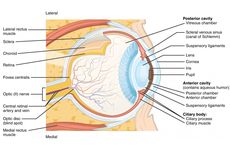

Jaringan yang menyusun organ mata pada manusia adalah jaringan ikat, jaringan saraf, jaringan otot, dan jaringan epitel